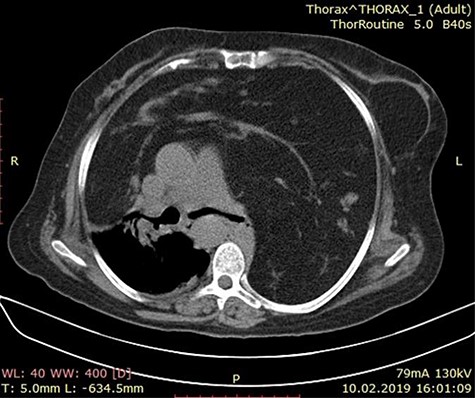

A 60-year-old female patient presented to the emergency with complains of dyspnea, non-productive cough and chest pain for 2 months. There is no history of hemoptysis, weight loss and substance abuse. On physical examination, oxygen saturation was 64%, blood pressure was 170/110 mm Hg, temperature was 97.9°F (36.6°C) and blood sugar was normal. Local examination of the chest revealed limitation in chest movement and decreased tactile focal fremitus on both sides of the chest. On percussion, dullness on both sides of the chest was noticed. On auscultation, decreased breath sounds on both sides of the chest were detected and the apex beat of the heart was displaced on the right side. The blood tests performed in the emergency room were in normal range. She underwent radiological evaluation with chest X-ray that revealed diffuse infiltration on both lungs (Fig. 1). Thoracic echocardiography revealed huge mediastinal mass with dextrocardia. This was followed by chest computed tomography (CT) that showed bilateral diffuse mediastinal mass, which involves fatty tissue containing soft tissue streaks that probably represent islands of normal thymic components with no infiltrations (Figs. 2–3). We concluded that the only curative treatment of thymolipoma is surgical excision. Unfortunately, despite the patient being told about the surgical procedure, she did not give the permission and passed away a week later due to secondary compression to the lungs.

Axial chest CT image showing a mass lesion with wide range of fat density filling both hemithorax was observed, including linear and nodular densities in the right hemithorax. A dense retrosternal mass displacing both lungs and chest. No evidence of invasion is seen.

CT scan of the chest showing a large anterior mediastinum mass projecting to the right and left hemithorax with wide range of fat tissue density.